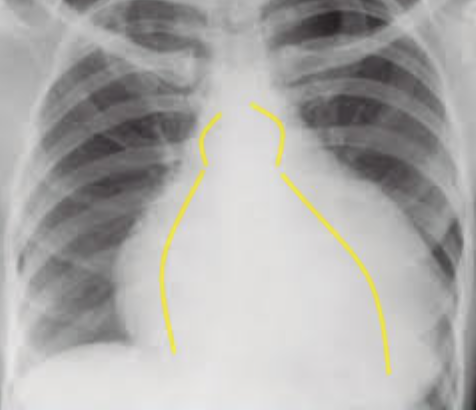

Pericardite - Exames de imagem (2)

A

Ecocardiograma: Para avaliar derrame pericárdico ou tamponamento;

Raio-X de tórax: Pode mostrar aumento da silhueta cardíaca se houver grande derrame;

Diagnóstico do processo inflamatório da pericardite (5)

Ecocardiograma (opção inicial + acessível): Para avaliar derrame pericárdico ou tamponamento;